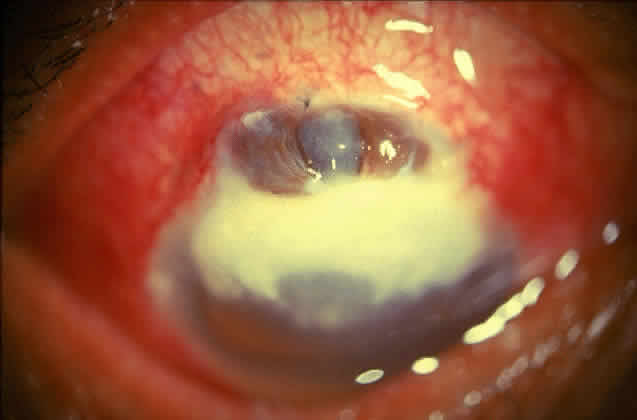

Fungal keratitis is as frequently seen as bacterial keratitis. Aspergillus and Fusarium are the two most commonly isolated organisms. Predisposing factors include trauma, foreign body, and injudicious usage of topical steroids or other indigenous medications.

Delay in diagnosis, the relative ineffectiveness of antifungal agents in most parts of the world, and the nonavailability of these drugs hinder prevention and management (Fig. 3).